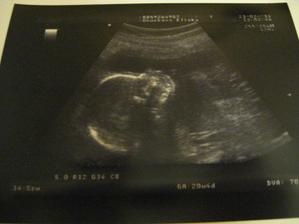

2. 3. 2011 Dneska jsme se byli vyfotit ve 3D 🙂 Chtěli jsme i video ale Kačenka měla půlnoc tak nebylo co točit 🙂